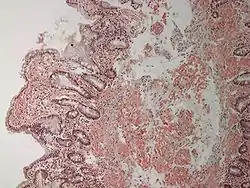

![]() Мікроскопічна картина патологоанатомічного препарату дванадцятипалої кишки з розвинутим амілоїдозом Мікроскопічна картина патологоанатомічного препарату дванадцятипалої кишки з розвинутим амілоїдозом | |

У кишечнику амілоїд утворюється в ретикулярній стромі слизової оболонки, а також у стінках судин як слизової, так і підслизової оболонок. При різко виразному амілоїдозі залозистий апарат кишок атрофується.